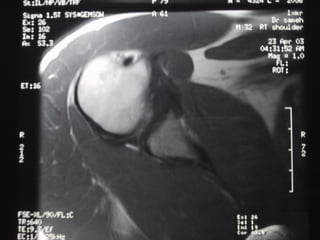

Case 5   Supraspinatus full thickness tear